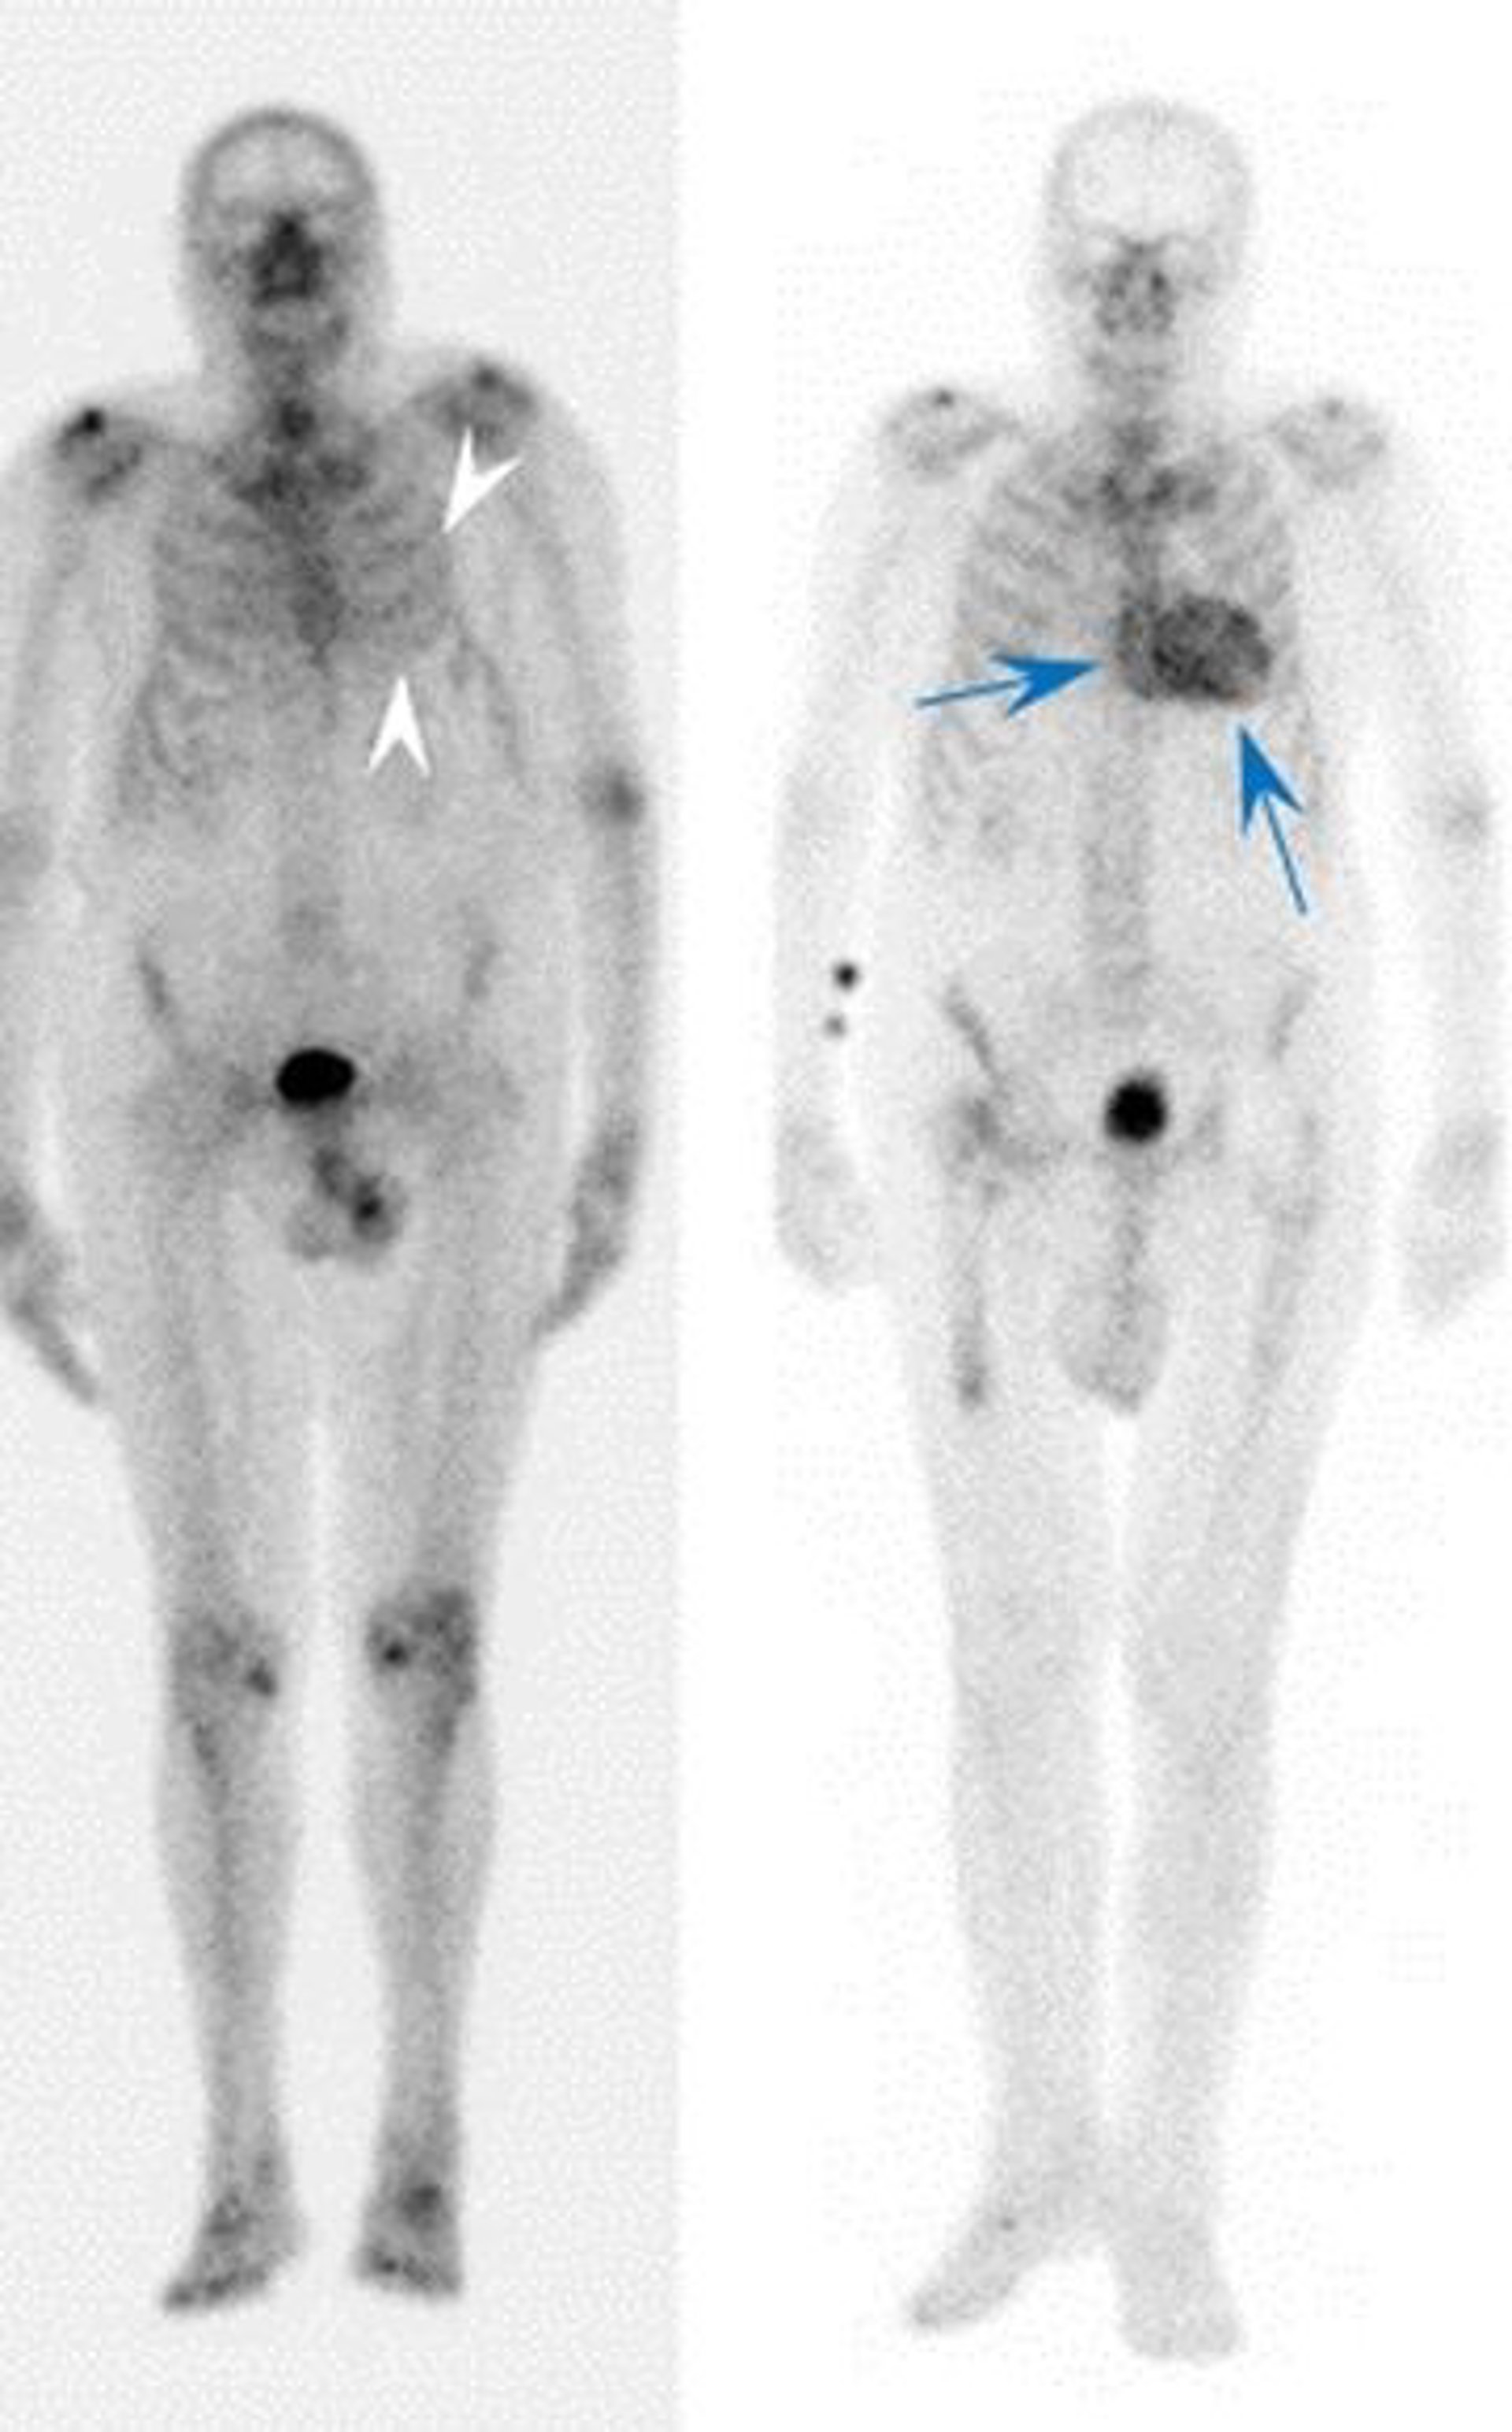

Para identificarlos, los autores usaron una técnica denominada gammagrafía con tecnecio-difosfonato, que se emplea en muchos hospitales pero que habitualmente se utiliza para identificar problemas a nivel de huesos y articulaciones.